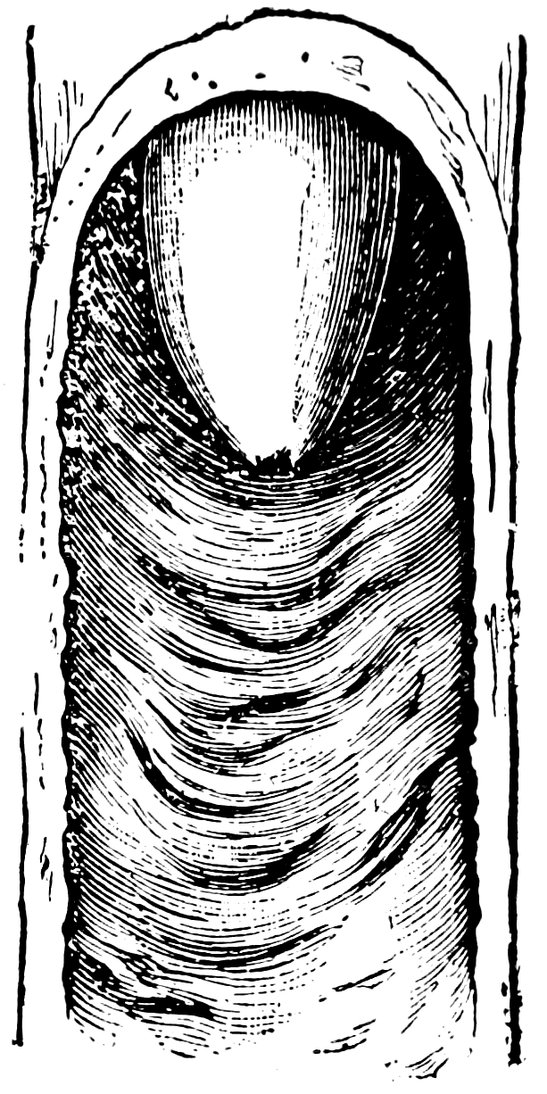

| 51. | Female internal genital organs in the fully developed state | 208 |

| 72. | Normal Shape of the Portio Vaginalis | 503 |